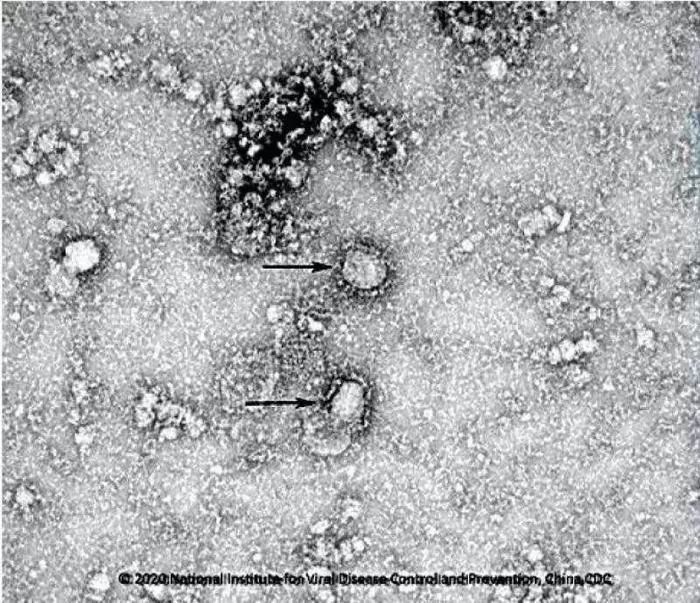

資料圖:新型冠狀病毒武漢株01 圖片來源:中國(guó)疾控中心網(wǎng)